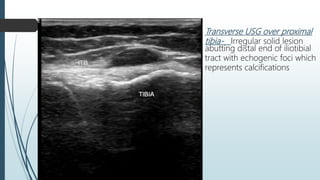

Transverse USG over proximal

tibia- Irregular solid lesion

abutting distal end of iliotibial

tract with echogenic foci which

represents calcifications